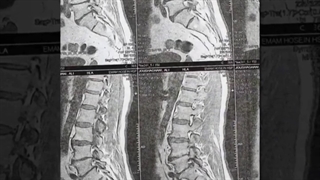

سرخوردگی شدید ستون فقرات و فشار مهره های کمر به نخاع جراحی موفقیت آمیز و رضایت بیمار پس از عمل.برای کسب اطلاعات بیشتر به وب سایت http://drghorbanimoghadam.com و یا ادرس مطب تهران، ولنجک، خیابان 14، پلاک 19، برج هوما مراجعه کنید .